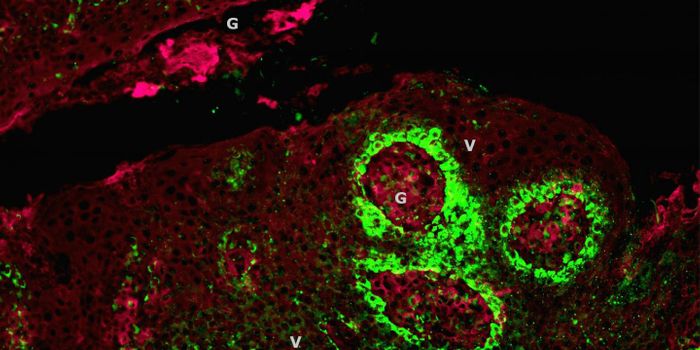

MAR 18, 2015Immunology

After a chance observation in the lab, researchers found a method that can force dangerous leukemia cells in the l ... -

JUL 25, 2022CancerAdvancements in immunotherapy have proven instrumental in reshaping the face of cancer research in recent years. W ...